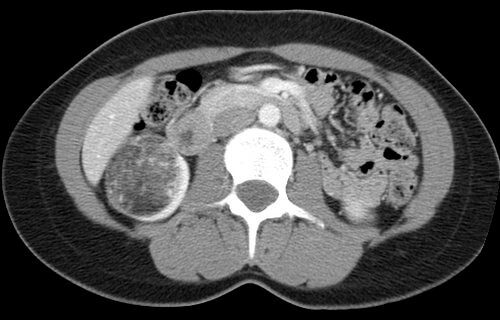

32 year old female who presents with an incidentally discovered right renal angiomyolipoma and undergoes prophylactic embolization.

Comment: This case demonstrates the classic appearance of an angiomyolipoma on CT and the hypervascularity associated with this benign tumor. The clearly seen abnormal vasculature enabled selective catheterization of the dominant supply to the angiomyolipoma and subsequent selective embolization with PVA particles. Embolization can be performed successfully with several types of particulate and/or liquid embolic agents. In this case, PVA was used successfully and no growth or viability has been seen on follow-up imaging after this procedure.